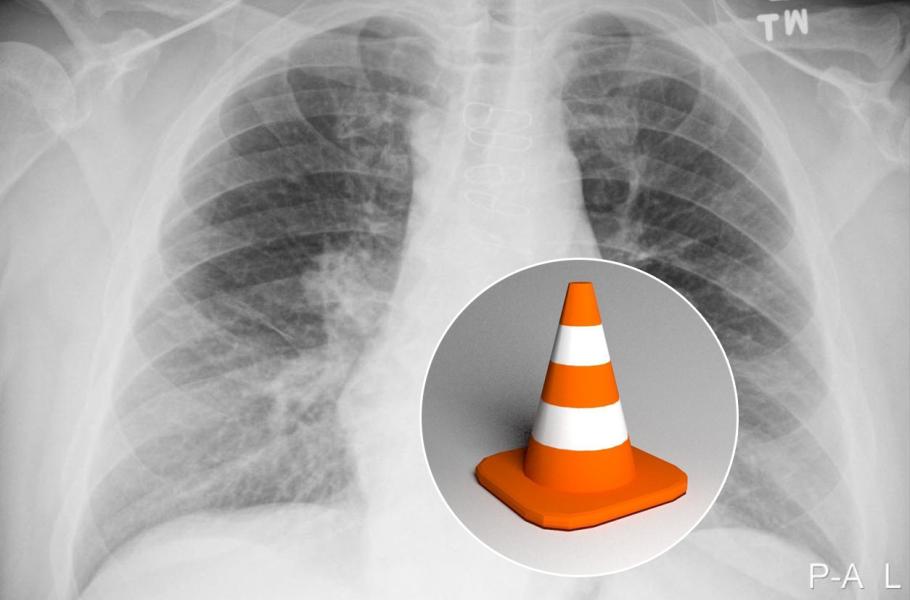

Dlouhý rok trápil jistého Brita z městečka Preston urputný kašel, až se konečně odhodlal navštívit lékaře. Rentgen odhalil na plicích neznámý objekt, a jelikož byl dotyčný kuřák, okamžitě padlo slovo „rakovina“. Podrobnější endoskopické vyšetření však ukázalo, že nejde o nádor, nýbrž o hračku – malý dopravní kužel.

Lékaři cizorodý předmět vyjmuli, nešťastníkovi se ulevilo a pod náporem emocí si vzpomněl, že se mu hračka ztratila ze sady, kterou dostal před 40 lety. Tehdy mu bylo sedm a sem tam spolkl nějaký drobný předmět – nějak mu ovšem „vypadlo“, že jeden z nich také vdechl. Odborníci prý neznají případ, kdy by se komplikace spojené s vdechnutím cizího tělesa projevily až po 40 letech, a neznámý muž je tedy svým způsobem také rekordman.